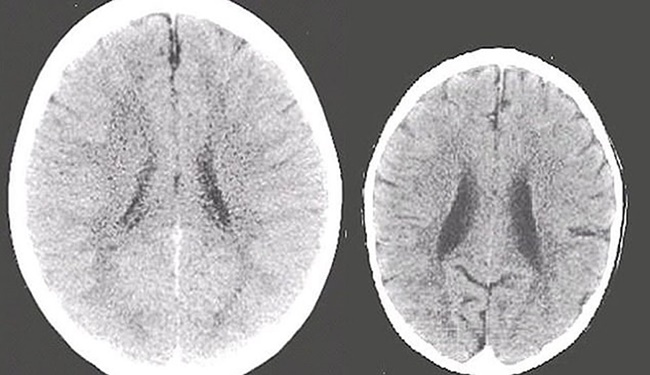

Bunu kanıtlamak için de ailesinin ilgisiyle büyüyen bir çocuk ile ilgisiz büyüyen 3 yaşındaki iki çocuğun beyin hareketlerini ve gelişimini gösteren tomografi sonuçlarını kullandı.Perry, “Fotoğraflarda da görüldüğü gibi sol taraftaki beyin taraması, ailesinin ilgisiyle yetişen ortalama bir çocuk beyni. Öte yandan sağ tarafta ailesiyle zaman geçirmeyen ve ailesinin ilgisini görmeyen bir çocuğun beyninin taraması var. Bu çocuğun şiddet görmüş olabileceğini de tahmin ediyoruz. Bu taramalar sonucunda, sağ taraftaki çocuğun beyni yaşıtına göre daha küçük” dedi.

Perry, “Sağ taraftaki çocuğun beyninin yeteri kadar gelişmemesi gelecekte hastalıkların da habercisi. Bu durum genelde Alzheimer hastası olan yaşlı bireyylerde görülür. Bu çocuğun hafıza sorunu yaşaması çok olası. Öte yandan bu çocuğun bağlanma sorunları ve sosyal olarak izole bir hayat sürmesi oldukça mümkün” şeklinde konuşarak ailelere uyarıda bulundu.